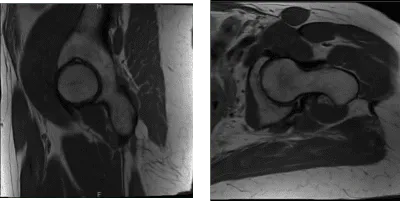

Presentó resultados de resonancia magnética en ambas caderas que mostraron tendinosis común leve en el isquiotibial con una pequeña rotura intrasustancial y edema circundante en la tuberosidad isquial. Necrosis avascular extensa de la cabeza femoral derecha. Cambios degenerativos en la parte baja de la columna lumbar de su cadera izquierda.

Necrosis avascular extensa que afecta la mayor parte de la cabeza femoral derecha y edema de médula ósea circundante que se extiende hasta el cuello femoral. La línea de fractura subcondral en forma de media luna se observa medialmente sin colapso o fragmentación articular.

Existen cambios osteofíticos leves en la articulación acetabular femoral derecha y un derrame articular moderado. Tendinosis leve del gluteo mínimo sin desgarro, para la cadera derecha.

Resonancia magnética Sin contraste en la cadera izquierda

Resonancia magnética Sin contraste en la cadera derecha